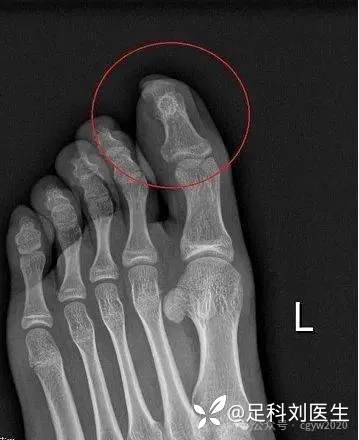

诊断通常需要X线检查,其特征性表现为末节趾/指骨远端大小不一的骨性隆起,骨密度与正常相似,顶端可能呈现杯形、圆形或不规则形 。MRI检查和皮肤活检也可以辅助诊断,但最终确诊依赖于肿物切除后的病理检查 。

Fig. 1A–D Clinical photographs and radiographs of the same subungual exostosis in the right hallux of a 15-year-old girl presenting with pain and an enlarging mass for 3 months. (A) Dorsal and (B) medial clinical photographs and (C) posterior-anterior and (D) lateral radiographs of the same lesion. Reproduced with permission from BMJ Case Reports.

图1A-D 15岁女孩右拇同一跖下外骨增生的临床照片和x线片,表现为疼痛和肿物扩大3个月。(A)背部和(B)内侧临床照片(C)前后位和(D)侧位x线片。经英国医学杂志病例报告许可转载。